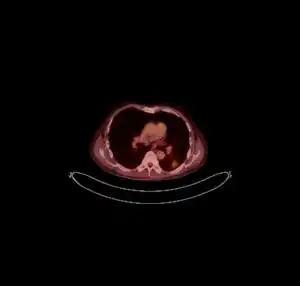

CT scan lungs: mass in right upper lobe -

FDG PET/CT - Multiple nodules (some cavitating) in the left lower lobe